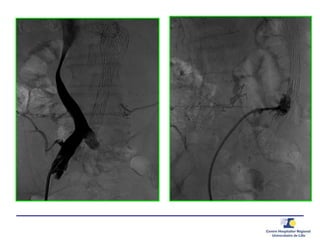

Anévrysmographie

• Angiographie

• Embolisation Type 2

• Embolisation iliaque interne + jambage

d’extension iliaque